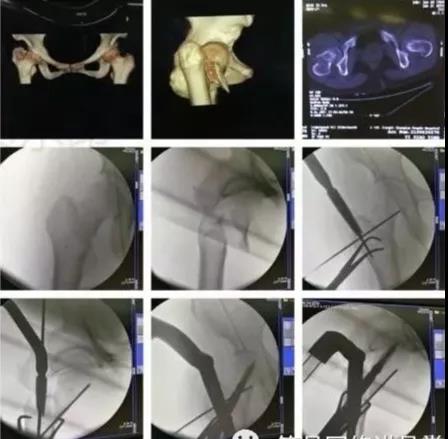

1)股骨近端(股骨头,颈,转子部位)

- <65岁,内固定;>65岁,关节置换。

- 患者全身情况稳定,应早期内固定。

- 内固定方式很多,如DHS,pfna等。